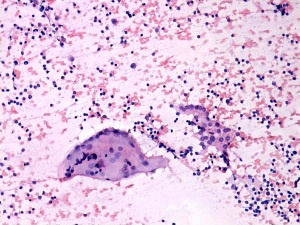

Combined cytological-clinical-sonographic diagnosis: Hashimoto's thyroiditis and Hürthle-cell tumor.

Histopathology disclosed Hashimoto's thyroiditis and Hürthle-cell adenoma.

Although follicular cells display atypia and prominent nucleoli, the cytological picture itself is not suspicious. Taking the sonographic pattern into account, the patient must have had a follicular-type tumor with great probability.